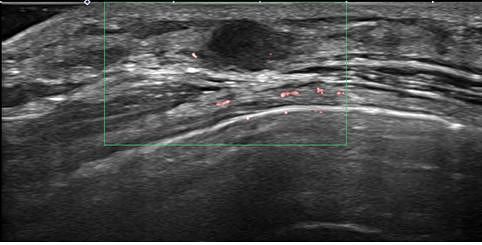

조기 유방암 환자의 초음파 검사 사진

유방촬영술은 유방암 검진의 가장 기초적인 검사 방법으로, 미세 석회화를 가장 잘 검사하는 방법이다. 유방암과 연관된 미세 석회화는 초음파나 MRI에서 보이지 않는 경우가 있어 유방촬영술 검진은 반드시 받아야 한다. 한국인은 유방 조직이 치밀한 치밀 유방을 가진 경우가 많은데 이것도 유방암의 발병 원인 중 하나다. 치밀 유방인 경우에는 유방 초음파가 도움이 된다. 고위험군이라면 필요시 MRI 검사를 시행하게 되며 영상학적 검사 이후 필요하다면 조직 검사를 통해 유방암을 진단한다.